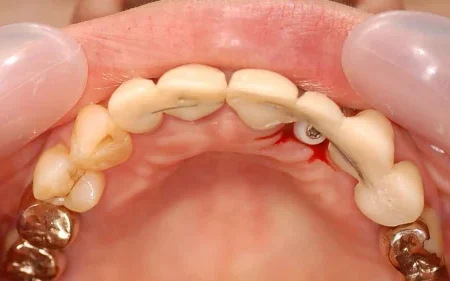

骨の厚みが薄いのでインプラントは現状難しい状態でした。

前歯は見える部分なので、手術中もできるだけ見た目が悪くならないように工夫しています。